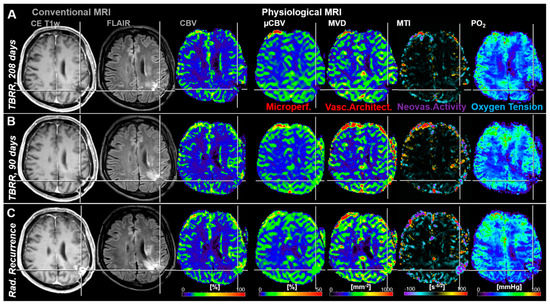

3.2. Follow-Up Examinations with Conventional and Physiological MRI

3.3. Time Courses of MRI Biomarker Changes Preceding Radiological AG Recurrence